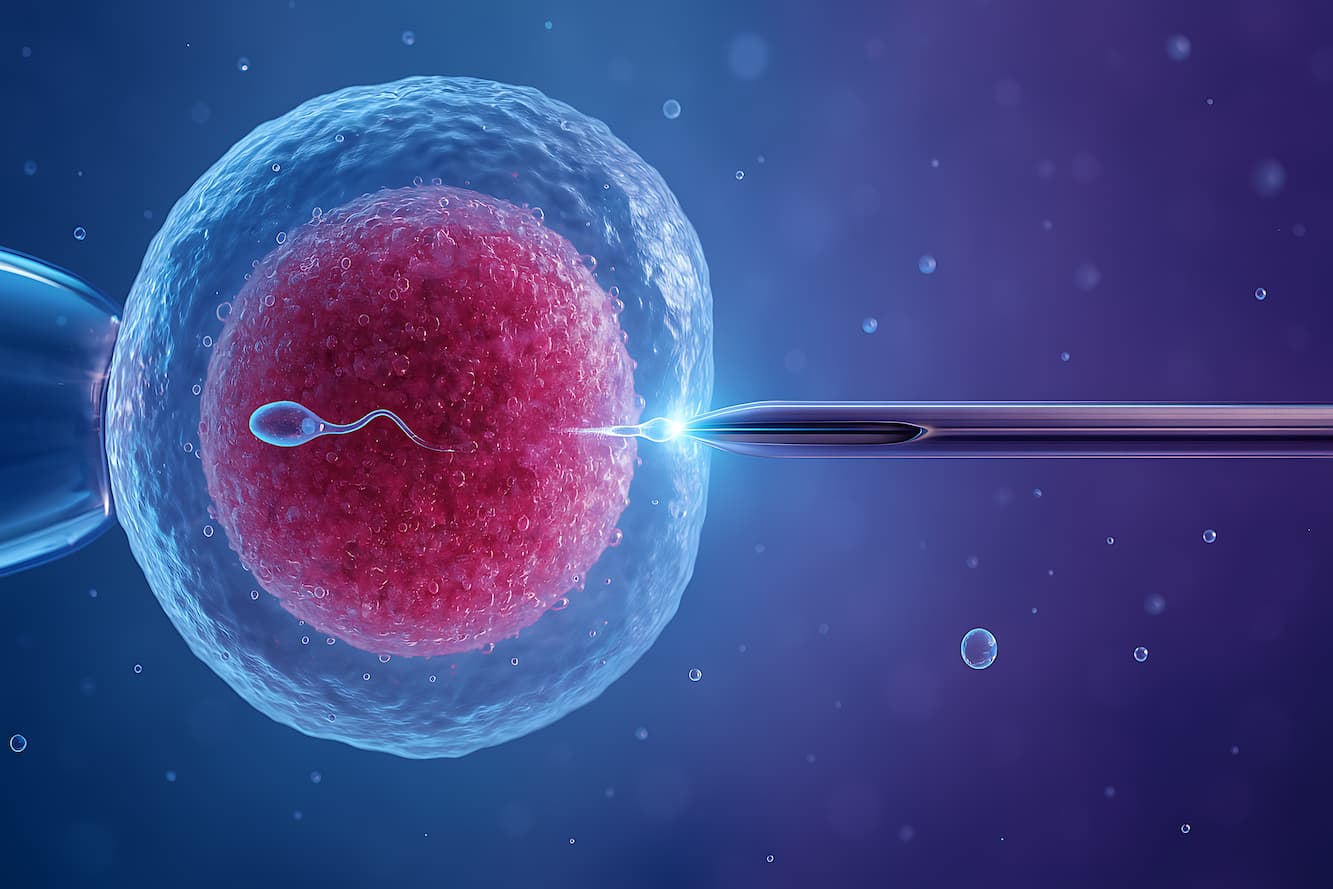

In Vitro Fertilization (IVF) is the most widely used form of assisted reproductive technology. This procedure involves extracting eggs from a woman’s ovaries and combining them with sperm in a laboratory setting, often resulting in fertilization.

In Vitro Fertilization (IVF) is the most widely used form of assisted reproductive technology. This procedure involves extracting eggs from a woman’s ovaries and combining them with sperm in a laboratory setting, often resulting in fertilization.